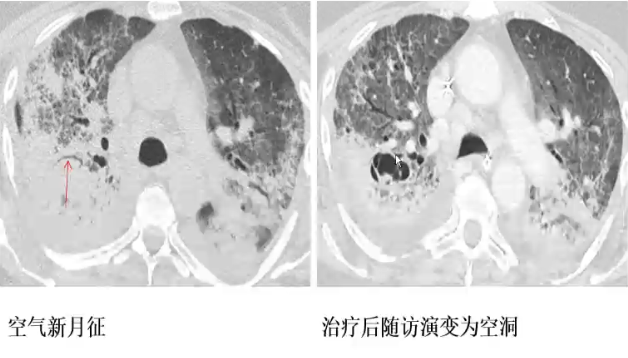

血管侵袭性曲霉菌病

❖ 结节伴晕征

❖ 以胸膜为基底的楔形实变(出血性梗死)

❖ 治疗后2-3周左右,肺实变或结节影内出现新月形(空气新月征)或圆形空洞(梗死肺组织回缩)

❖ HS和ACS无特异性,但在粒缺患者中高度提示曲霉菌感染